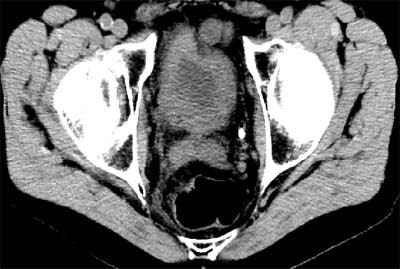

At least a third of his screening clients have HMO coverage, Brant-Zawadzki said, displaying an image of a patient with back pain that had not been prolonged or severe enough to warrant a CT scan from the managed care plan. The diagnosis was hydronephrosis and bladder cancer.

| Above and below: Bladder cancer is detected in a 67-year-old male CT screening patient who presented with back pain. Images courtesy of Dr. Michael Brant-Zawadzki. |